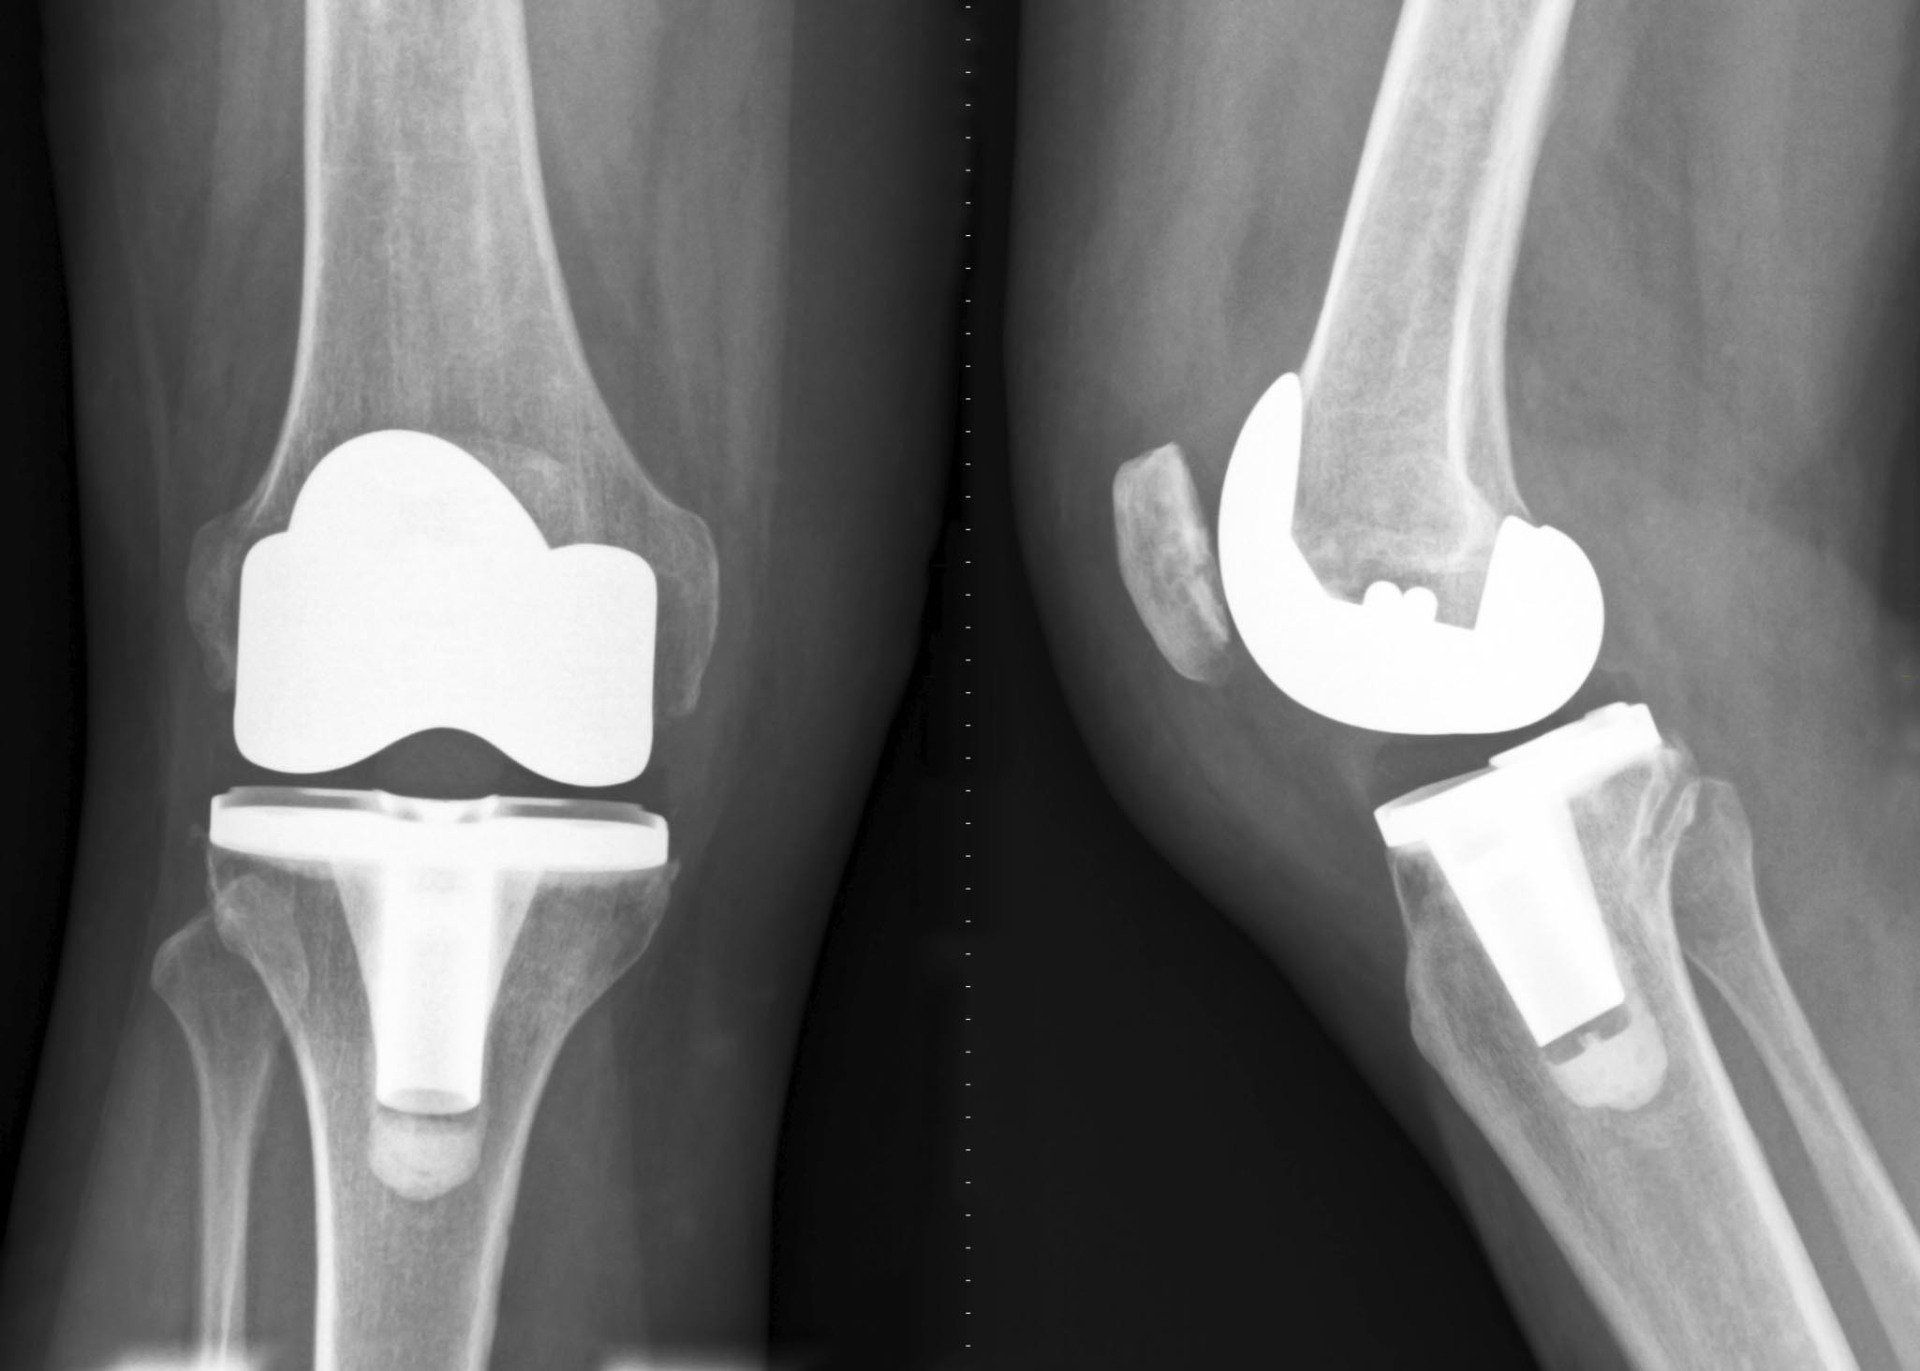

Auf der operativen Seite ergänzt er unser ambulantes und stationeres OP-Team in der Schulter,- Hand,- und Kniechirurgie.

Gerade Im Bereich der Schulter- und Kniechirurgie ist er auf Minimalinvasive Eingriffe spezialisiert.